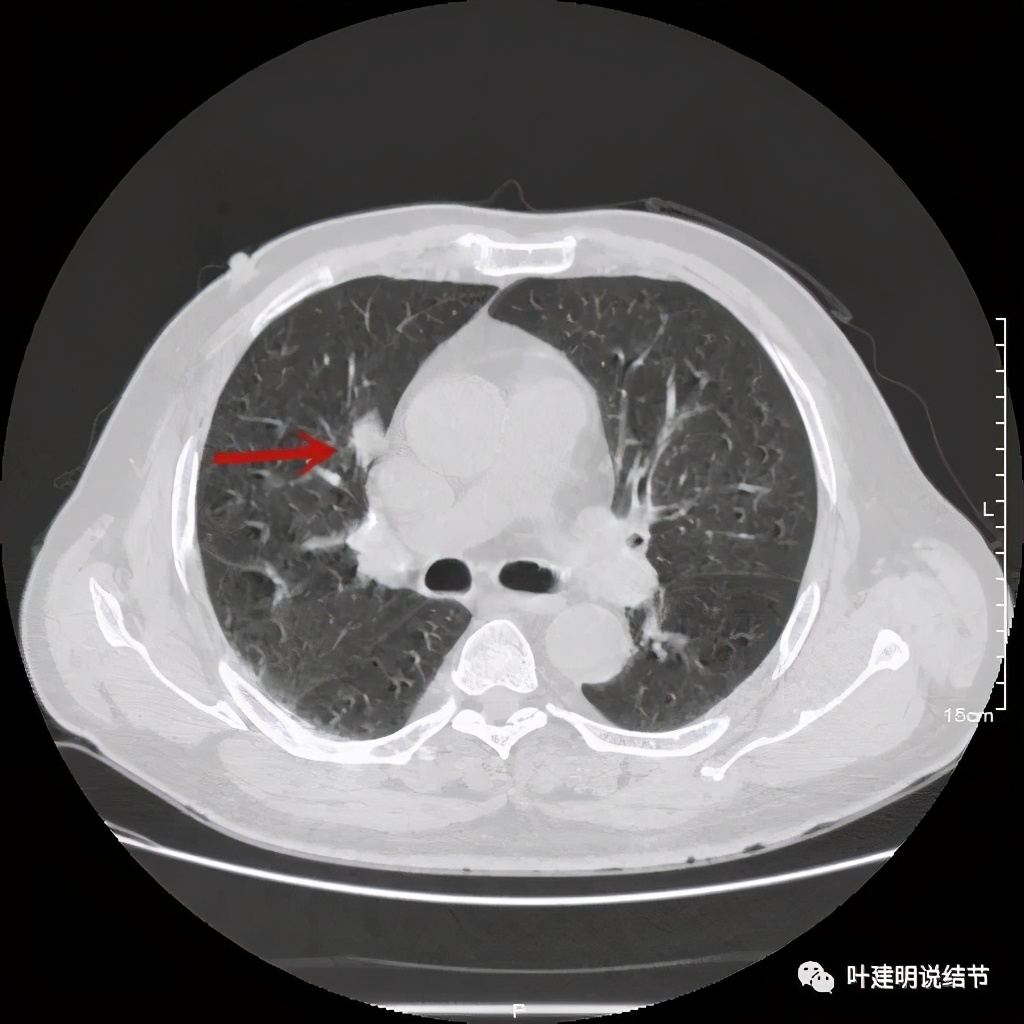

病灶在上图层面似见支气管也是贴壁的。那么增强后又是如何呢?

事前来看,达2.4厘米的不均质实性肿块,增强有轻度不均匀强化,血管贴边走行,支气管疑有截断,恶性不能除外,而且可能性较大。但现在经过手术已已经证实是错构瘤的情况下,我们回头来看,其实有许多不符合恶性的地方:

1、病灶的每个层面,边缘都过于光滑了。肺癌一般到这个大小总要有棘突、分叶、毛刺、牵拉周围胸膜等边缘异常的征象;

2、肿瘤大于2厘米以上,又紧贴血管,多有血管走行异常、受侵或血管进入等征象;